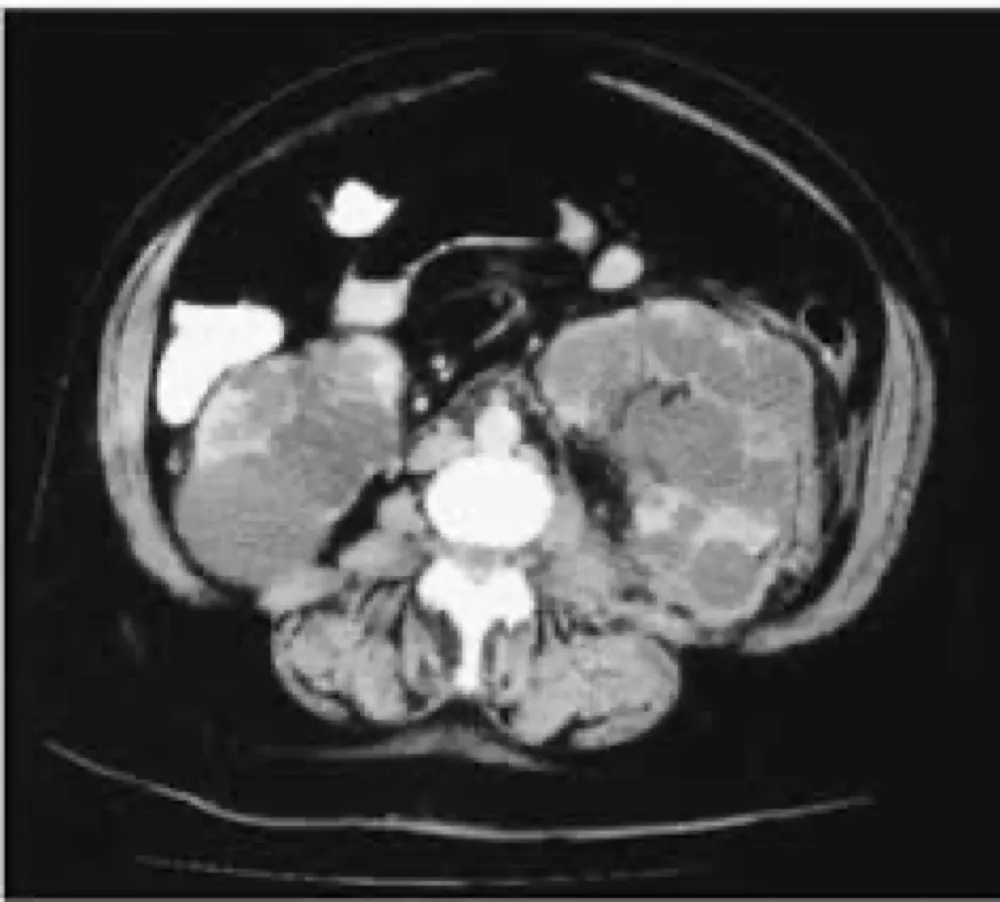

A DRPAD não é contraindicação à DP — e, na prática, muitos pacientes têm resultados comparáveis à hemodiálise. O “porém” está na mecânica: rins/hepatomegalia podem reduzir tolerância a volumes, aumentar risco de hérnias e extravasamentos, e piorar desconforto respiratório. Com técnica adequada (cateter presternal ou lateral, volumes menores, cicladora noturna e decúbito supino), a maioria das barreiras é contornável. Neste post, revisamos quando a DP é ótima, quando exigir cautela e como ajustar a prescrição para segurança e qualidade de vida.

Uso do Tolvaptan na Doença Renal policística, dicas de prescrição!

Tolvaptan é um medicamento indicado para retardar a progressão da doença renal policística autossômica dominante (DRPAD). Ele age reduzindo o crescimento dos cistos renais e requer monitoramento regular devido a possíveis efeitos adversos, como hepatotoxicidade e desidratação. Sua prescrição é indicada para pacientes com alto risco de progressão da doença. Confere aqui as dicas práticas de prescrição e seguimento.